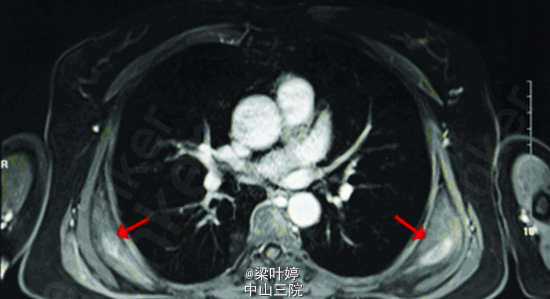

查体:双侧肩胛下角区域可扪及一直径约5cm 硬质类圆形包块,固定。余无特殊。 CT提示:双侧背阔肌及前锯肌深面对称性病变,增强后不均匀强化,周围脂肪间隙清楚。 MRI示::双侧对称性病变,位于背阔肌及前锯肌深面,增强后斑片状强化,周围脂肪间隙清晰,局部与肋骨骨膜关系紧密。